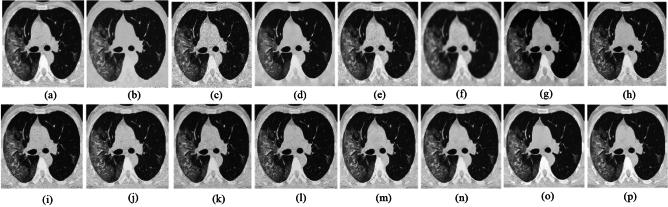

Medical imaging systems such as computed tomography (CT) and magnetic resonance imaging (MRI) are vital tools in clinical diagnosis and treatment planning. However, these modalities are inherently susceptible to Gaussian noise introduced during image acquisition, leading to degraded image quality and impaired visualization of critical anatomical structures. Effective denoising is therefore essential to enhance diagnostic accuracy while preserving fine details such as tissue textures and structural boundaries. This study proposes a robust and efficient denoising framework specifically designed for CT and MRI images corrupted by Gaussian noise. The method integrates a cluster-wise principal component analysis (PCA) thresholding approach guided by the Marchenko-Pastur (MP) law from random matrix theory and a non-local means algorithm. Noise level estimation is achieved globally by analysing the statistical distribution of eigenvalues from noisy image patch matrices and leveraging the MP law to accurately determine the Gaussian noise variance. An adaptive clustering technique is employed to group similar patches based on underlying features such as textures and edges and enables localized denoising operations tailored to heterogeneous image regions. Within each cluster denoising is performed in two stages where initially hard thresholding based on the MP law is applied to the singular values in the SVD domain to obtain a low-rank approximation that preserves essential image content while removing noise-dominated components. Residual noise in the low-rank matrix is then further suppressed through a coefficient-wise linear minimum mean square error LMMSE estimator in the PCA transform domain. Finally, a non-local means algorithm refines the denoised image by computing weighted averages of pixel intensities and prioritizing neighbourhood similarity over spatial proximity to effectively preserve edges and textures while reducing Gaussian noise. Experimental evaluations on CT and MRI datasets demonstrate that the proposed method achieves superior denoising performance while maintaining high structural similarity and perceptual quality compared to existing state-of-the-art approaches. The method demonstrates adaptability noise reduction capability and preservation of anatomical detail that make it well suited for precision critical medical imaging applications.

计算机断层扫描(CT)和磁共振成像(MRI)等医学成像系统是临床诊断和治疗规划中的重要工具。然而,这些模态在图像采集过程中固有地容易受到高斯噪声的影响,导致图像质量下降以及关键解剖结构的可视化受损。因此,有效的去噪对于提高诊断准确性同时保留诸如组织纹理和结构边界等精细细节至关重要。本研究提出了一种强大且高效的去噪框架,专门针对受高斯噪声破坏的CT和MRI图像设计。该方法集成了一种由随机矩阵理论中的马尔琴科 - 帕斯图尔(MP)定律引导的聚类主成分分析(PCA)阈值处理方法和一种非局部均值算法。通过分析噪声图像块矩阵的特征值统计分布并利用MP定律来准确确定高斯噪声方差,实现全局噪声水平估计。采用自适应聚类技术根据纹理和边缘等潜在特征对相似块进行分组,并针对异质图像区域进行局部去噪操作。在每个聚类中,去噪分两个阶段进行,首先在奇异值分解(SVD)域中基于MP定律应用硬阈值处理奇异值,以获得保留基本图像内容同时去除噪声主导成分的低秩近似。然后在PCA变换域中通过系数线性最小均方误差(LMMSE)估计器进一步抑制低秩矩阵中的残余噪声。最后,非局部均值算法通过计算像素强度的加权平均值并优先考虑邻域相似性而非空间邻近性来细化去噪图像,从而在减少高斯噪声的同时有效保留边缘和纹理。对CT和MRI数据集的实验评估表明,与现有的最先进方法相比,所提出的方法在保持高结构相似性和感知质量的同时实现了卓越的去噪性能。该方法展示了适应性降噪能力和解剖细节保留能力,使其非常适合精密关键的医学成像应用。